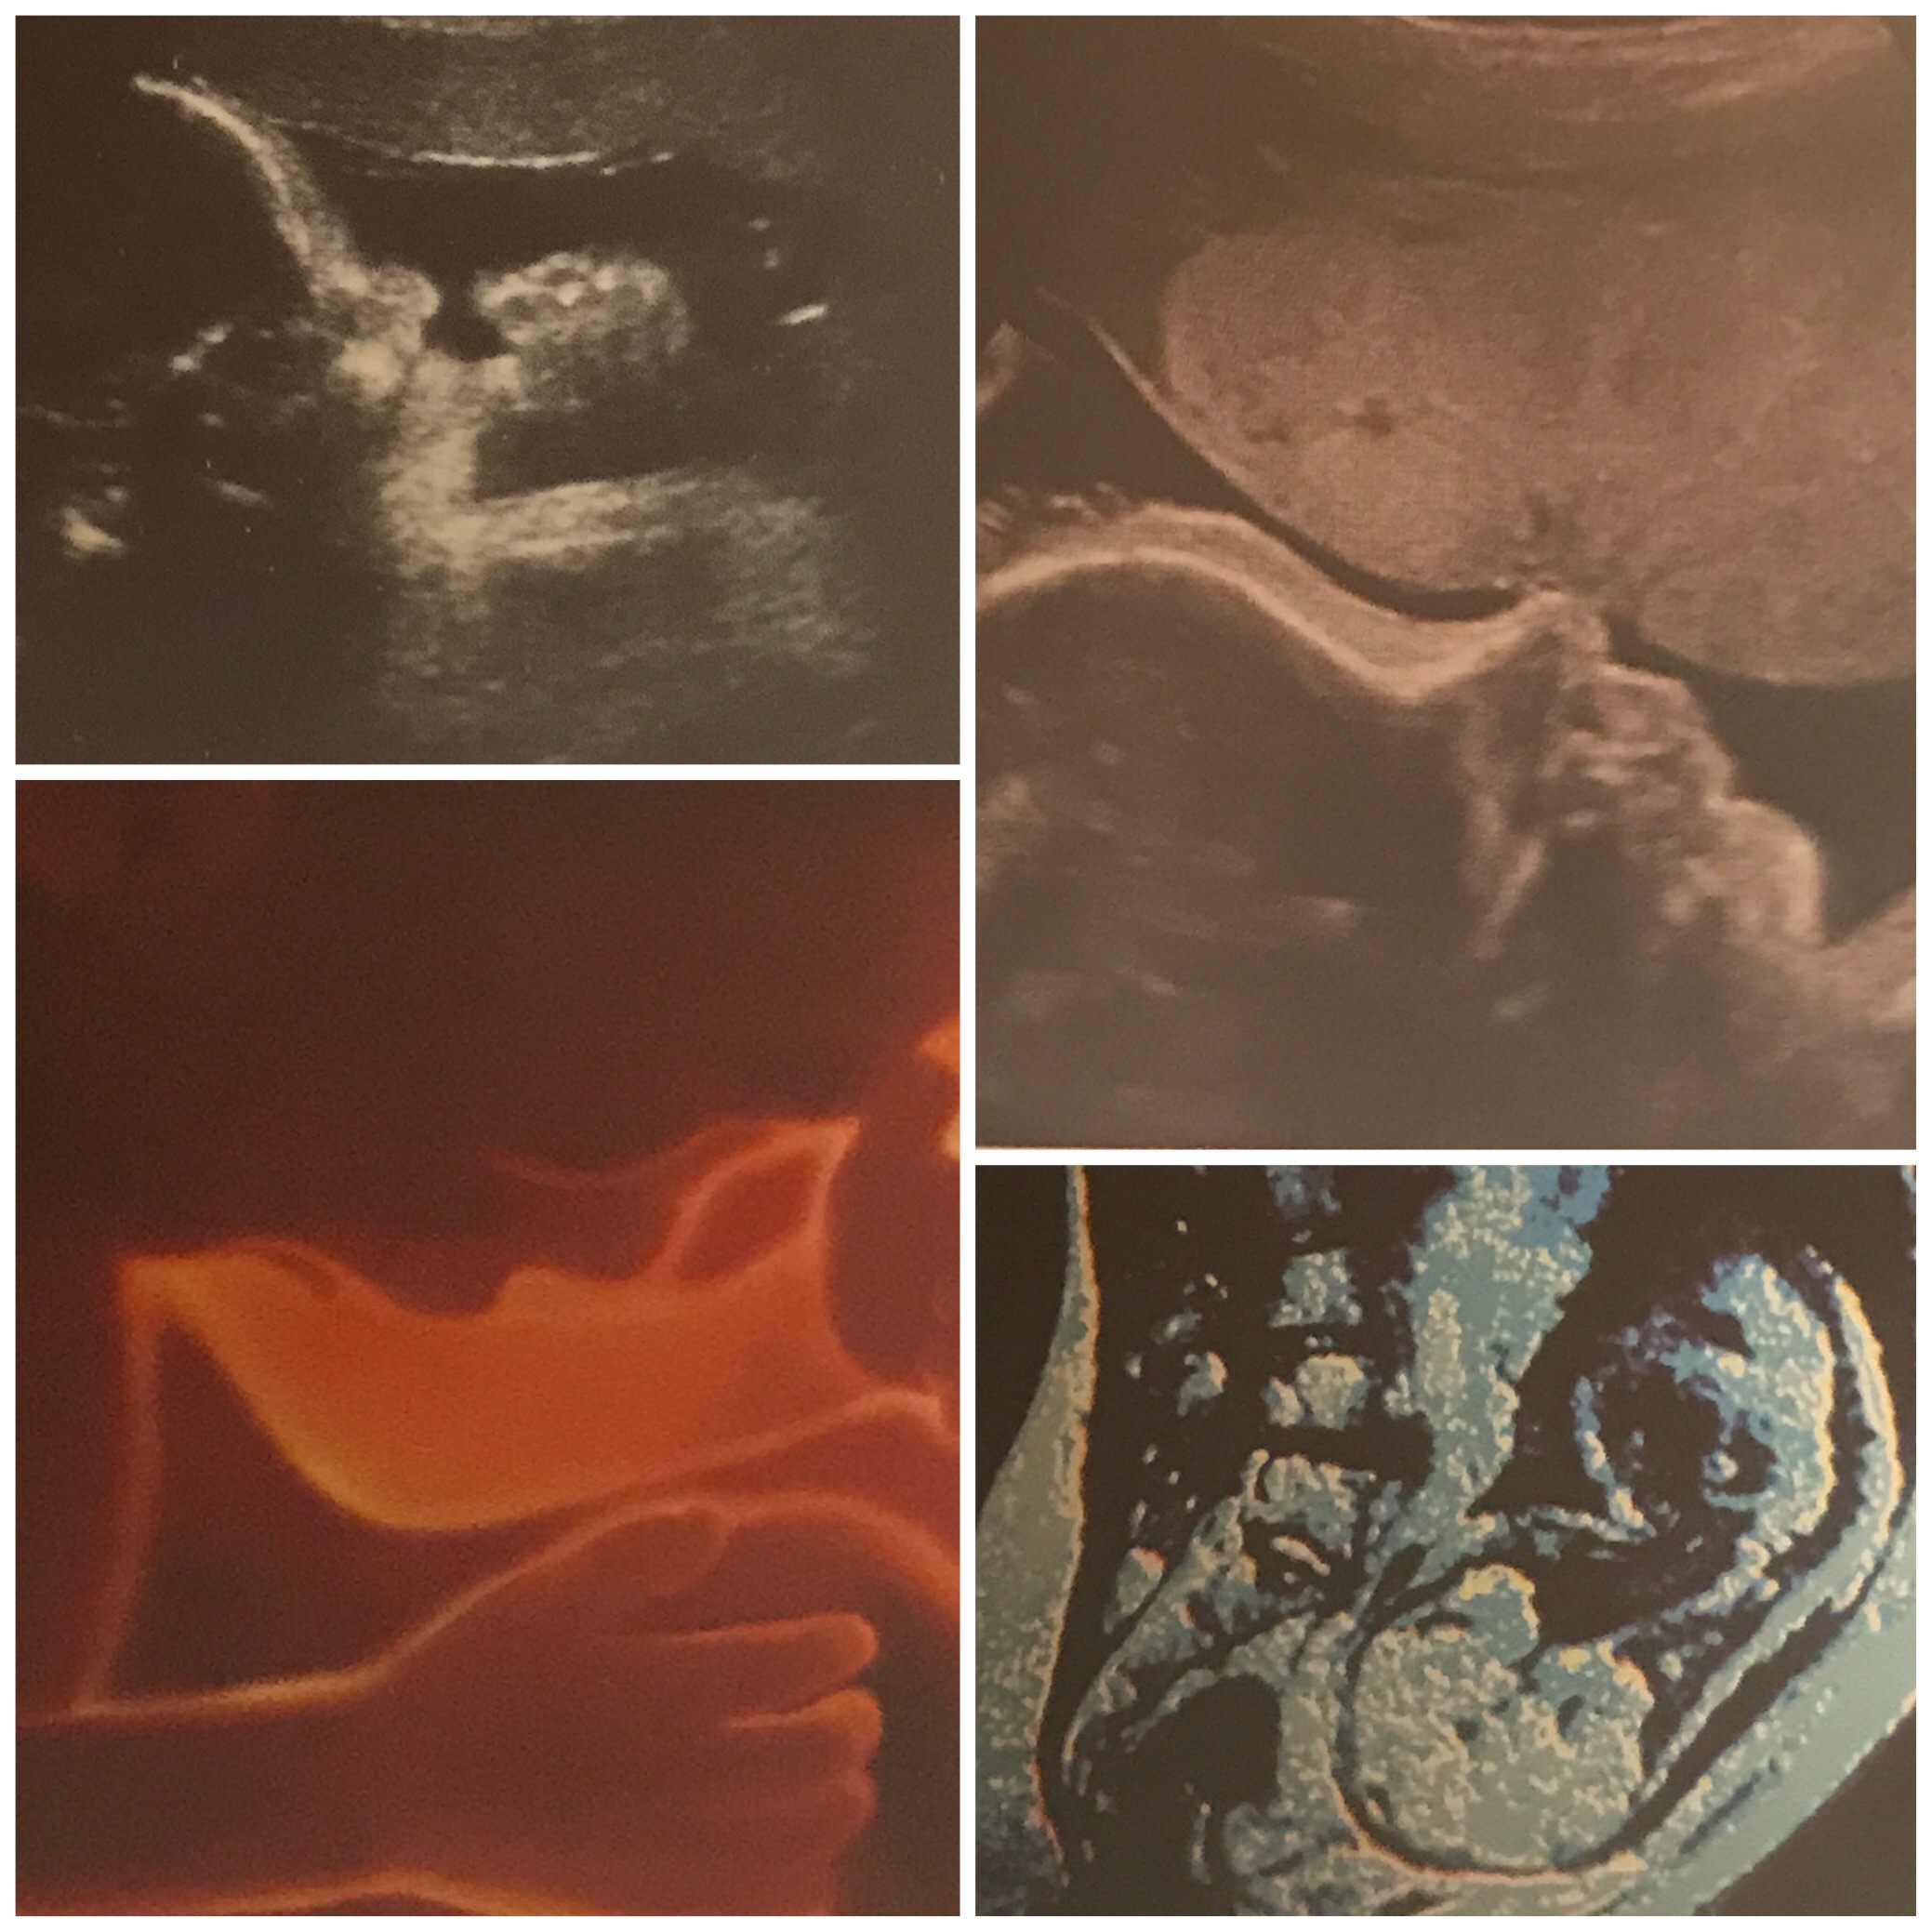

This week our baby’s central nervous system matures even more as do his or her lungs. His or her skin will smooth out, and additionally fat layers which help regulated internal body temperature are getting larger.

The placenta will not get any bigger at this point. As I’ve noted before Gestational Diabetes fasting numbers may be a little harder to control in the next two weeks, and in fact, I did have to up my Insulin units last night, though, at week 36 and beyond they tend to stabilize.